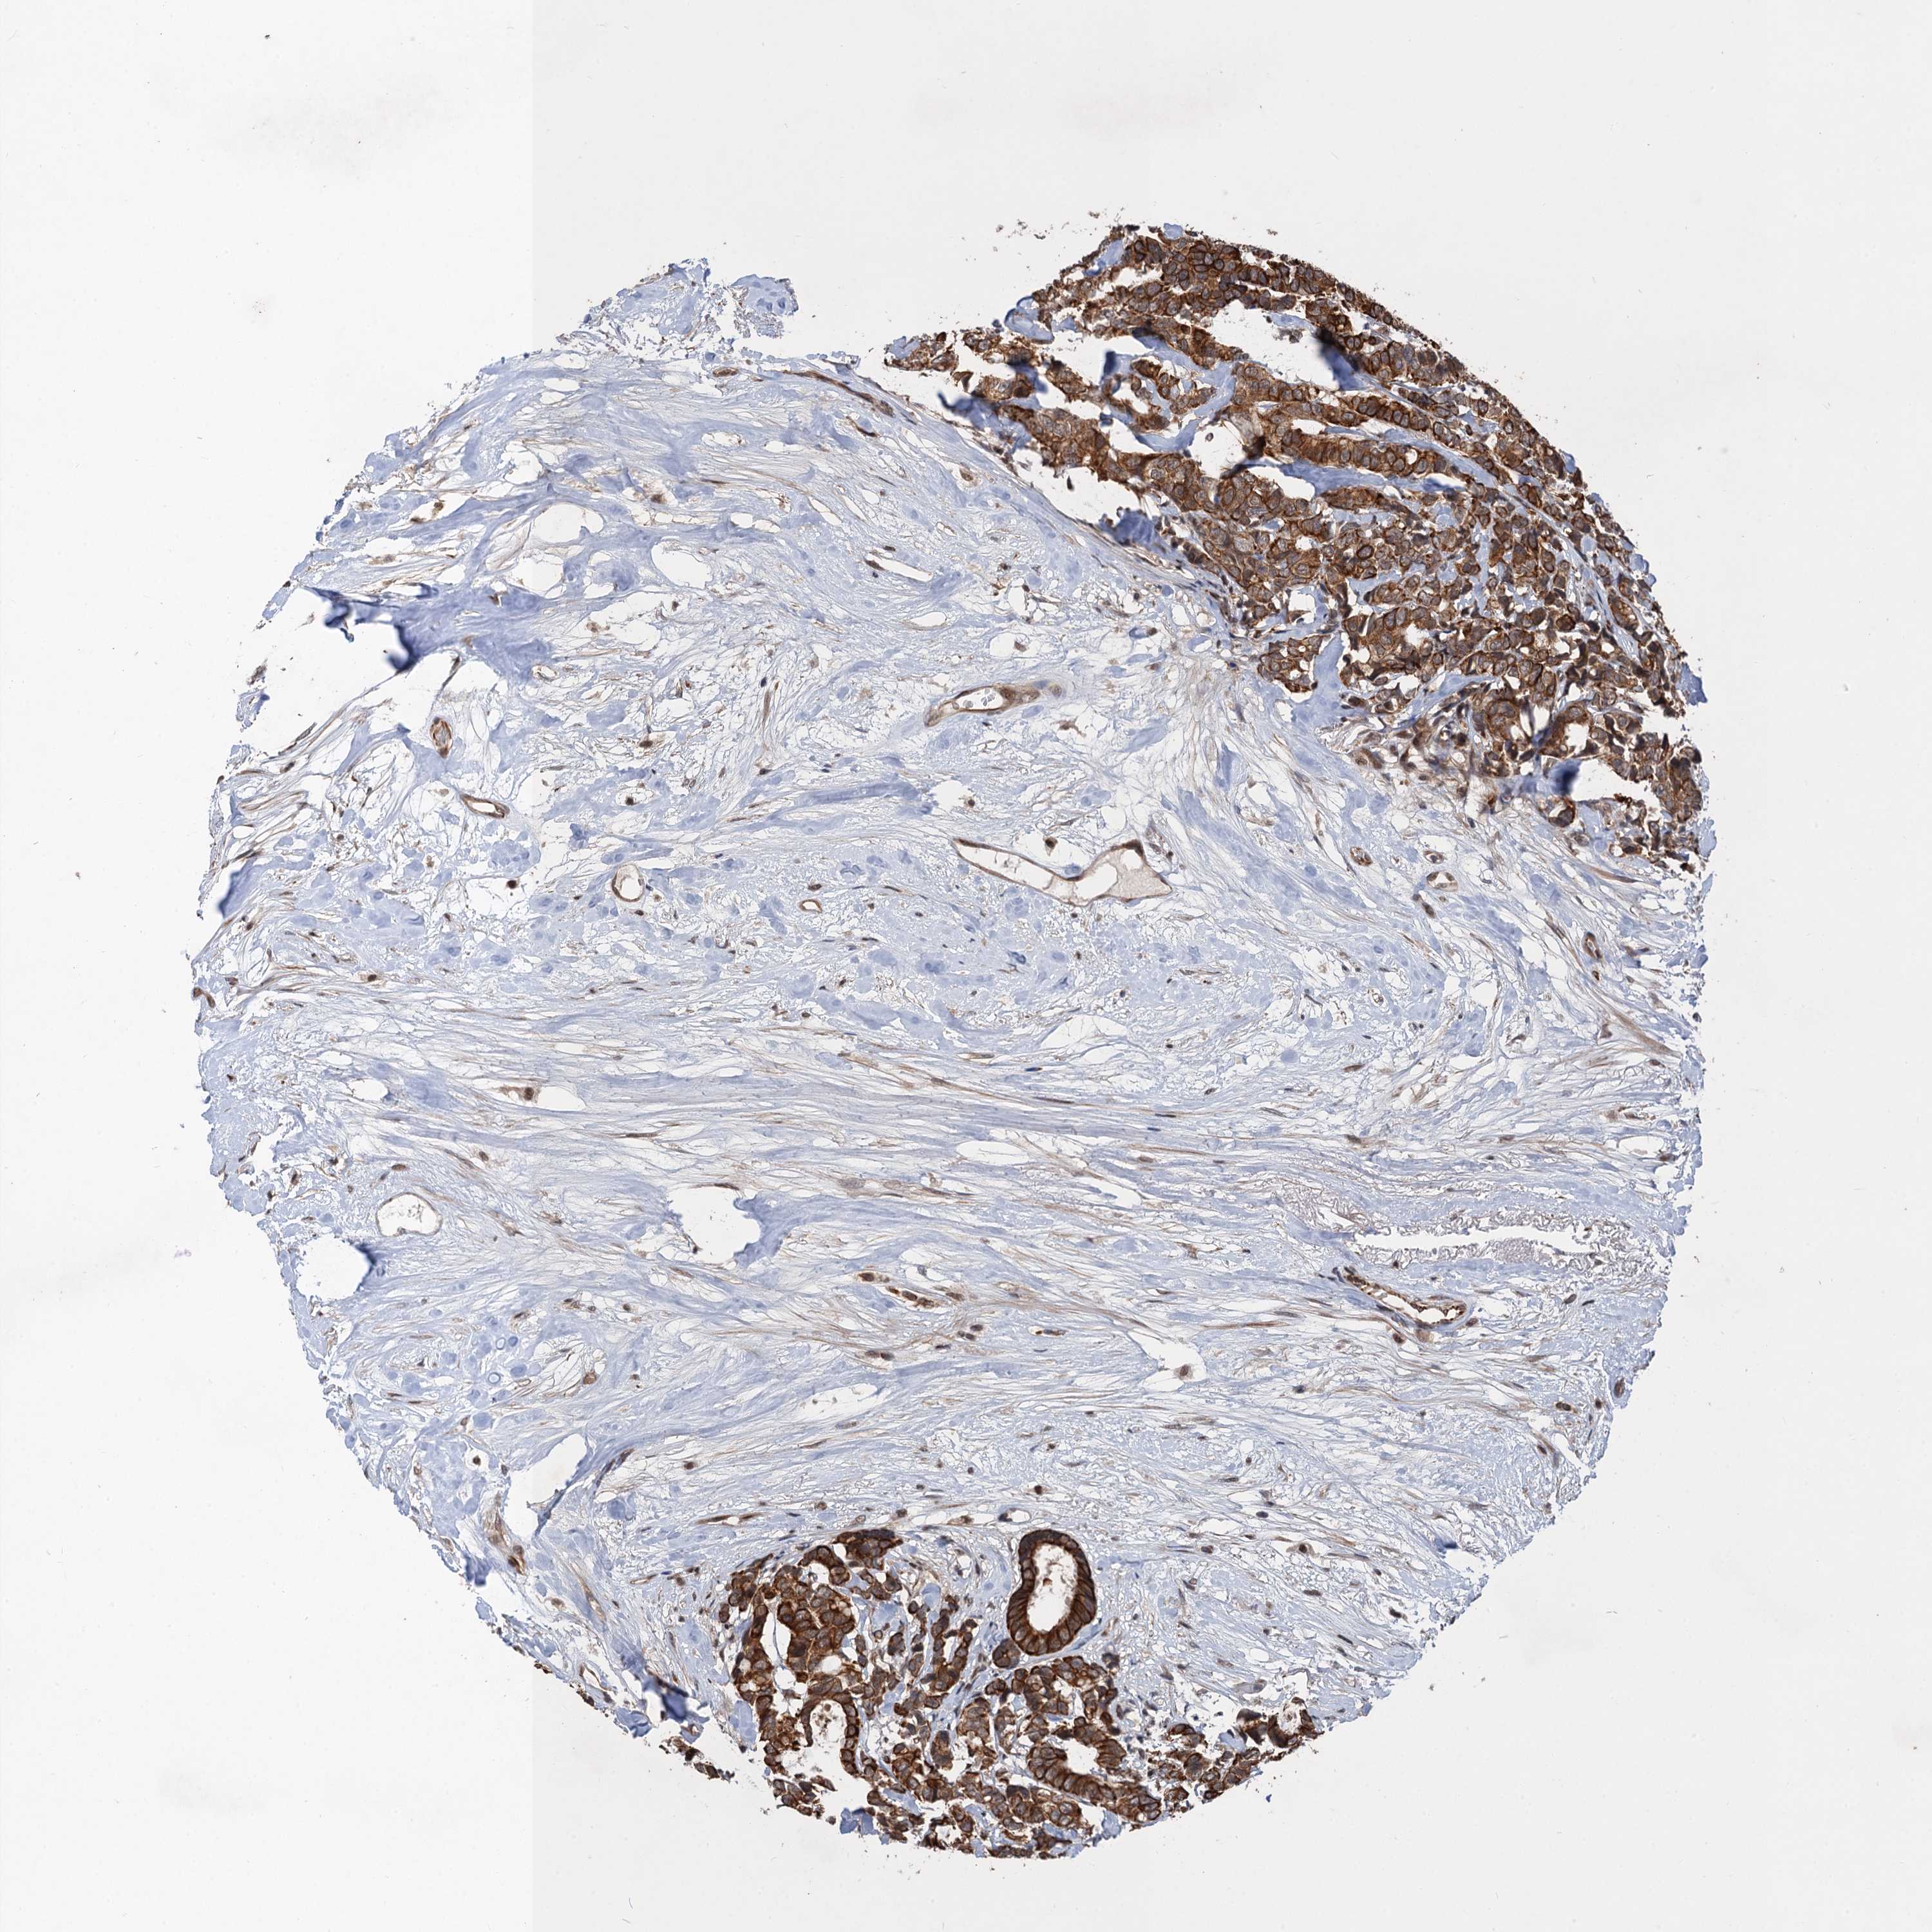

CANCER BREAST CANCER Show tissue menu

BRCA TCGA BRCA VALIDATION PROTEIN EXPRESSION